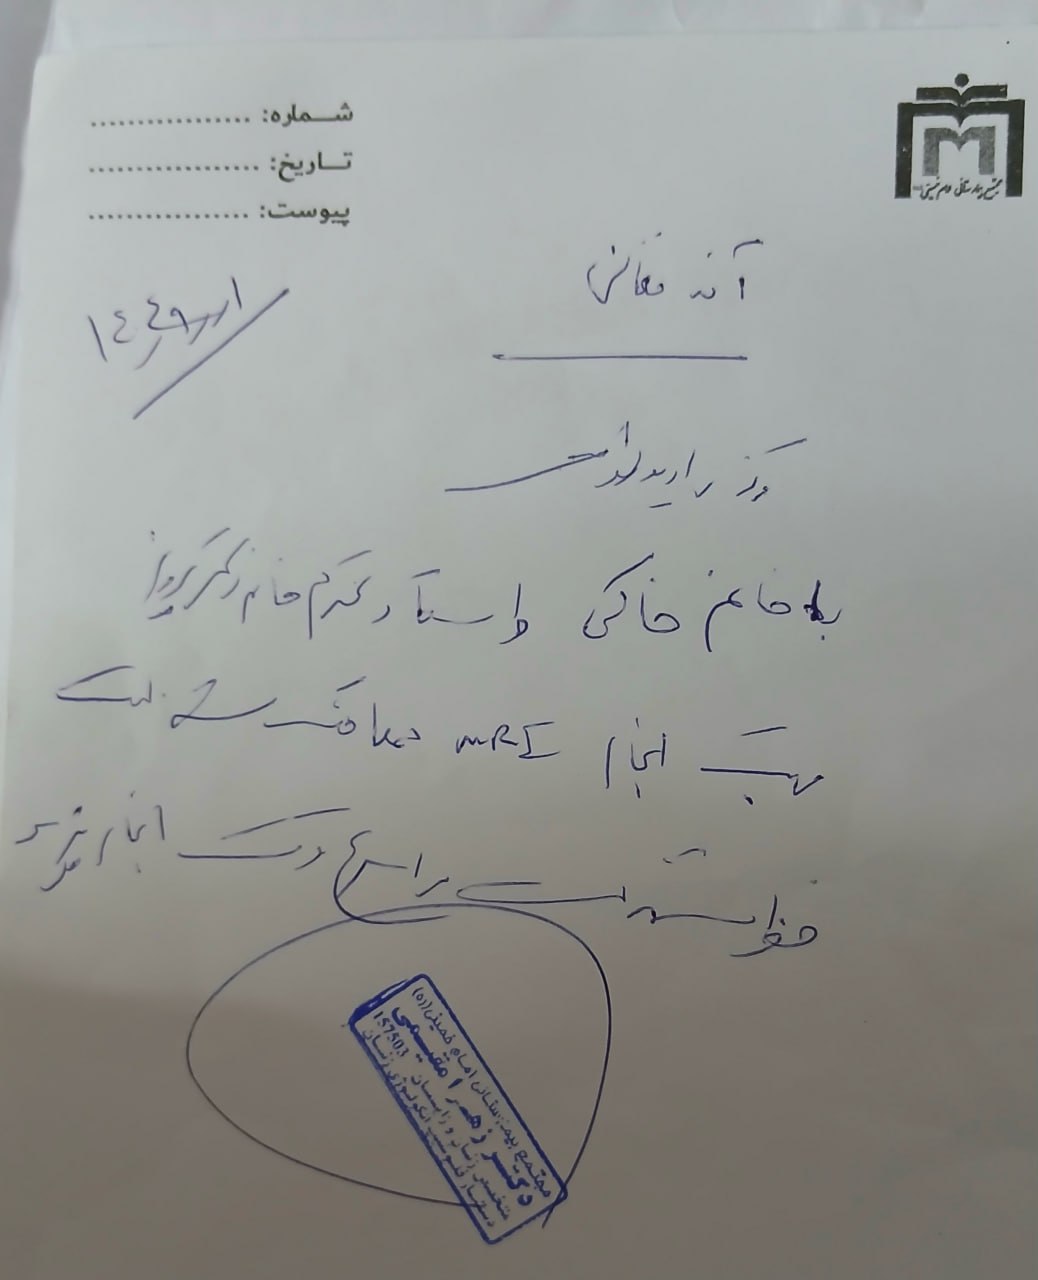

(تصویر مربوط به این مراجعه نیست) Other:

(تصویر مربوط به این مراجعه نیست) Other:

(تصویر مربوط به این مراجعه نیست) Other:

(تصویر مربوط به این مراجعه نیست) Other:

(تصویر مربوط به این مراجعه نیست) Other:

(تصویر مربوط به این مراجعه نیست) Other:

(تصویر مربوط به این مراجعه نیست) Other:

(تصویر مربوط به این مراجعه نیست) Other:

(تصویر مربوط به این مراجعه نیست) Other:

(تصویر مربوط به این مراجعه نیست) Other:

(تصویر مربوط به این مراجعه نیست) Other:

(تصویر مربوط به این مراجعه نیست) Other:

(تصویر مربوط به این مراجعه نیست) Other:

(تصویر مربوط به این مراجعه نیست) Other:

(تصویر مربوط به این مراجعه نیست) Other:

(تصویر مربوط به این مراجعه نیست) Other:

(تصویر مربوط به این مراجعه نیست) Other:

(تصویر مربوط به این مراجعه نیست) Other:

(تصویر مربوط به این مراجعه نیست) Other:

(تصویر مربوط به این مراجعه نیست) Other:

(تصویر مربوط به این مراجعه نیست) Other:

(تصویر مربوط به این مراجعه نیست) Other:

(تصویر مربوط به این مراجعه نیست) Other:

(تصویر مربوط به این مراجعه نیست) Other:

(تصویر مربوط به این مراجعه نیست) Other:

(تصویر مربوط به این مراجعه نیست) Other:

(تصویر مربوط به این مراجعه نیست) Other:

(تصویر مربوط به این مراجعه نیست) Other:

(تصویر مربوط به این مراجعه نیست) Other:

(تصویر مربوط به این مراجعه نیست) Other:

(تصویر مربوط به این مراجعه نیست) Other:

(تصویر مربوط به این مراجعه نیست) Other:

(تصویر مربوط به این مراجعه نیست) Other:

(تصویر مربوط به این مراجعه نیست) Other:

(تصویر مربوط به این مراجعه نیست) Other:

(تصویر مربوط به این مراجعه نیست) Other:

(تصویر مربوط به این مراجعه نیست) Other:

(تصویر مربوط به این مراجعه نیست) Other:

(تصویر مربوط به این مراجعه نیست) Other:

(تصویر مربوط به این مراجعه نیست) Other:

(تصویر مربوط به این مراجعه نیست) Other:

(تصویر مربوط به این مراجعه نیست) Other:

(تصویر مربوط به این مراجعه نیست) Other:

(تصویر مربوط به این مراجعه نیست) Other:

(تصویر مربوط به این مراجعه نیست) Other:

(تصویر مربوط به این مراجعه نیست) Other:

(تصویر مربوط به این مراجعه نیست) Other: